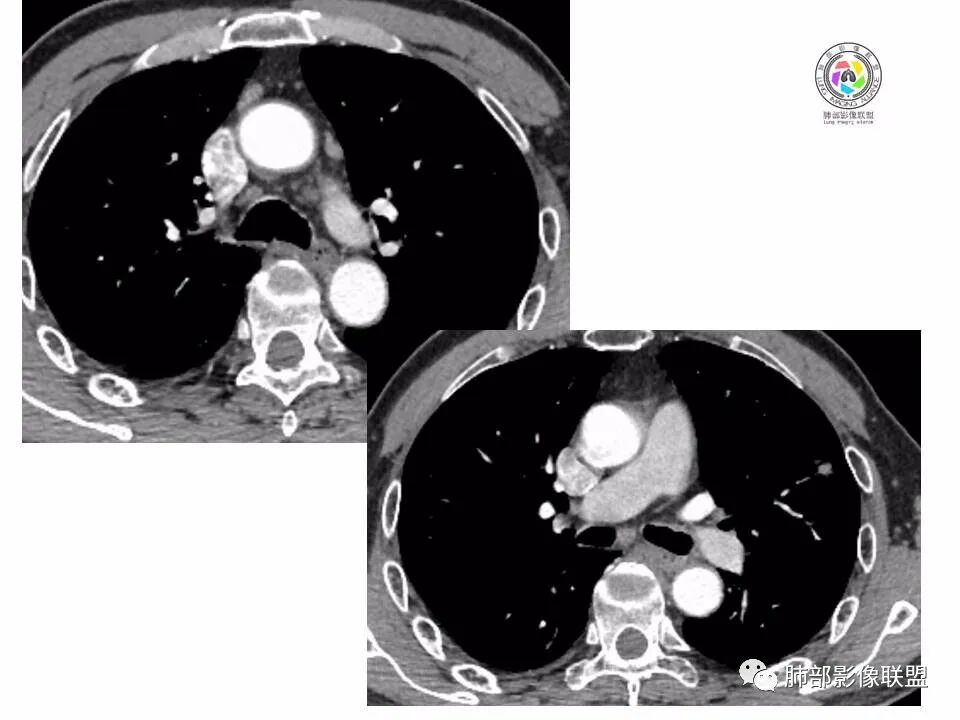

左肺上叶小结节,边缘毛糙,血管集束,支气管截断,强化较明显,但U型凹陷,部分边缘平直,总体感觉恶性大于良性,首选腺癌,鉴别炎性肉芽肿。

左上肺结节,月牙征,边缘纠集有收缩力,小空泡,血管增粗进入,纵隔淋巴结增大,考虑恶性,隐球菌待排。

老年男性,左上肺结节,边缘毛糙,临近血管进入增粗,内部隐约可见小空泡或远端扩张支气管,血管集束并伴月牙铲,有个横断界面看似像脐凹征,常规考虑腺癌,鉴别隐球。

结节,分叶,边缘毛糙,小空泡,血管集束并伴月牙铲,有强化,老年男性,考虑腺癌,建议复查除外结核。

左肺上叶混合密度结节,边缘见边缘清楚磨玻璃,分叶,U型凹陷,首先考虑腺癌。

左肺上叶结节影,边缘可见分叶,血管集束及月牙铲征,病灶内见小空泡影,考虑腺癌可能。

结节密度不均匀,混合磨玻璃结节,大部分实性部分,边缘清,月牙铲征,肿瘤微血管征,考虑肺癌。

老年男性,体检发现左肺上叶结节,周围浅分叶伴磨玻璃影,有血管相连,U型凹陷,纵隔见肿大淋巴结,考虑为恶性,腺癌可能。

左肺形态不规则结节,边缘收缩,毛刺,有月牙铲,纵隔窗比肺窗小,不密实,近段血管与病灶相连,强化不明显,老年男性,综合考虑,恶性,腺癌,鉴别炎性结节。建议穿刺。

老年男性,左肺上叶结节,边界清,不规则,有毛刺,血管集束,空泡,边缘有气肿带,考虑腺癌,鉴别肉芽肿。

左肺上叶小结节,边缘毛糙,血管集束,支气管截断,有月牙铲,首选腺癌,鉴别炎性肉芽肿。

左上肺实性小结节,短毛刺,月牙铲,似见小空泡,血管集束,有轻度强化,首先考虑腺癌。

老年男性,肺气肿背景,左肺上叶小结节,大部分边缘平直,部分边缘膨隆,局部可见月牙铲,边缘少许磨玻璃,边界清晰,血管进入,轻度强化,首先考虑腺癌,常规抗炎后复查,除外炎性结节。

左上肺结节,短毛刺,空泡,月牙铲,脐凹征,考虑腺癌。

左肺上叶混合密度结节,边界清,分叶,毛刺,血管进入,月牙铲,有强化,首先考虑腺癌,有平直边,收缩力不明显,常规先抗炎。

左上肺结节分叶,边缘毛糙,小空泡可能,血管集束,月牙,纵隔窗面积小于肺窗,有磨玻璃成份,有强化,老年男性,白细胞高,恶性的征象都有,但磨玻璃的形态和边界不好评估,实性为主,看形态和边缘局部较散缺乏饱满感,顶着压力反着来猜炎性可能大。复查不消失会考虑腺癌或黏液腺癌。

老年男性,肺气肿背景,左肺上叶实性结节,边界清,边缘平直为主,细长毛刺,较明显强化,考虑炎性病灶,隐球?

老年男性,左肺上叶结节,边缘可见长毛刺、较软,并可见分叶,周围可见清楚磨玻璃密度,内可见空泡征,增强后呈均匀强化,良恶性征象都有,感觉收缩力不强,化验白细胞偏高,建议抗炎治疗后复查除外腺癌。

老年男性,左肺上叶混合密度结节,空泡,分叶,血管集束,有强化,考虑腺癌;细长软毛刺,血管走行自然,边缘有平直收缩,白细胞高,肿标正常,考虑炎性结节。猜炎性结节,鉴别腺癌。

左肺上叶前段mGGN,边缘见毛刺及月牙铲,考虑腺癌,需要薄层图像确认所见征象。

左肺上叶结节,分叶,边缘毛糙,小空泡,月牙铲,有强化,考虑浸润性腺癌,鉴别炎性肉芽肿。

患者老年男性,体检发现。查癌胚抗原不高。血常规血象升高。胸部CT:肺气肿背景,左肺上叶近胸膜下实性结节,边缘光滑,边界清楚,可见毛刺、血管集束、月牙铲征象,增强不明显,内可见低密度区,综合考虑恶性病变,腺癌可能大,鉴别结核及炎性结节。

老年男性,左肺上叶结节,周围浅分叶伴磨玻璃影,有血管相连,月牙铲。纵隔见肿大淋巴结,但白细胞高。腺癌首先,需排除炎性假瘤。抗炎治疗后复查。

老年男性,体检发现左肺结节,分叶、脐凹、月牙铲及月牙铲附近有边缘清楚的磨玻璃影,上述征像均指向恶性肿瘤,有疑问的地方:毛刺软无力,无胸膜牵拉及白细胞计数升高。整体是腺癌,需要抗议后复查以排除炎性病变。

图片有限,左肺上叶结节病灶,有张力,有收缩及小泡征,边缘可见月牙征,周围长毛刺及血管集束征,增强目测有中度以上强化,首先考虑恶性病变,腺癌。

左肺上叶前段小结节,边缘稍毛糙,月牙铲,血管进入可疑脐凹征,小空泡?增强有强化,老年男性,要高度警惕腺癌,但感觉毛刺偏细软,周围磨玻璃不明显,常规查隐球菌荚膜抗原除外隐球菌,血象高,抗炎后短期复查除外炎性结节。

左肺上叶mGGN,边缘收缩平直为主,肺窗显示清楚,纵隔窗体积缩小,未见胸膜牵拉,倾向感染性结节,隔期复查。